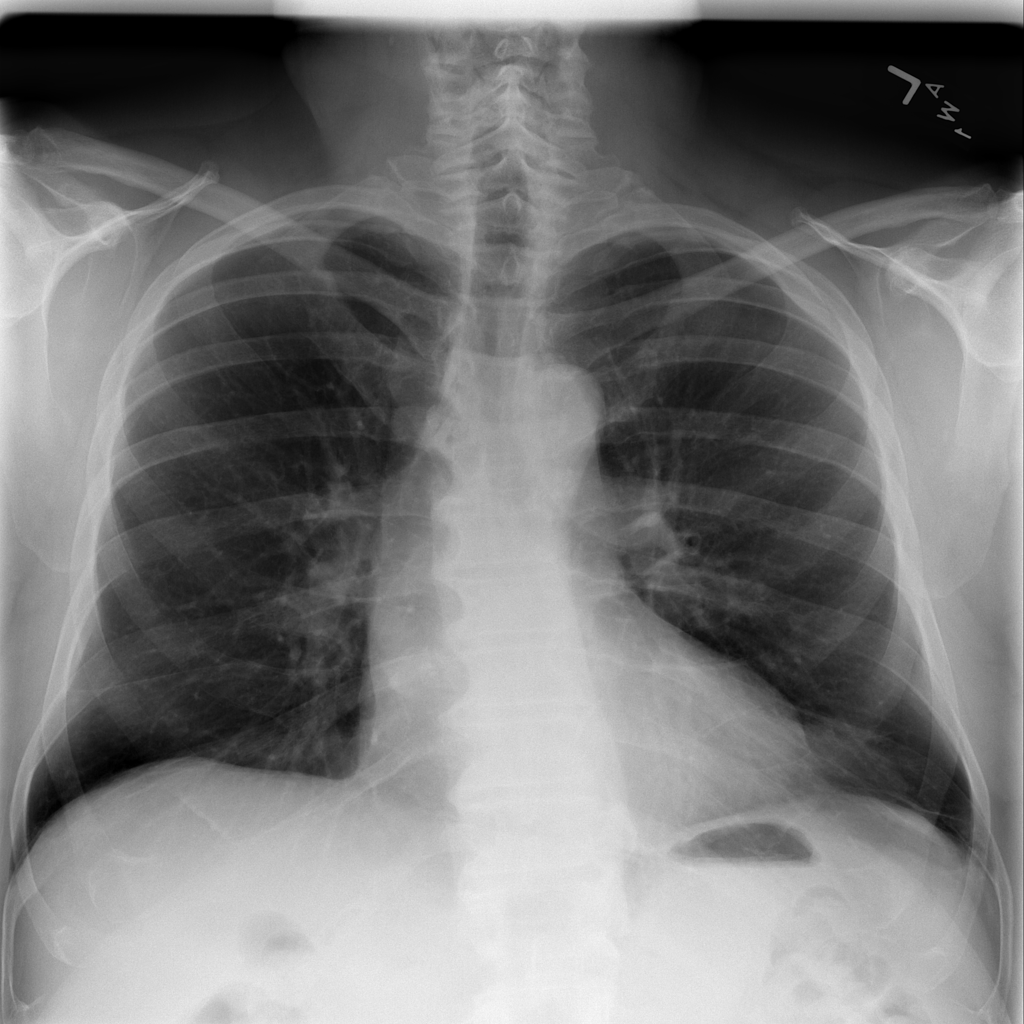

PAT-B625 · IMG-009Atelectasis

PAT-B625 · IMG-009

PA